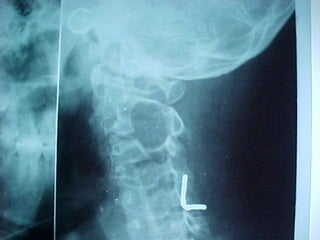

Diagnosis

 Plain X-ray

 MRI